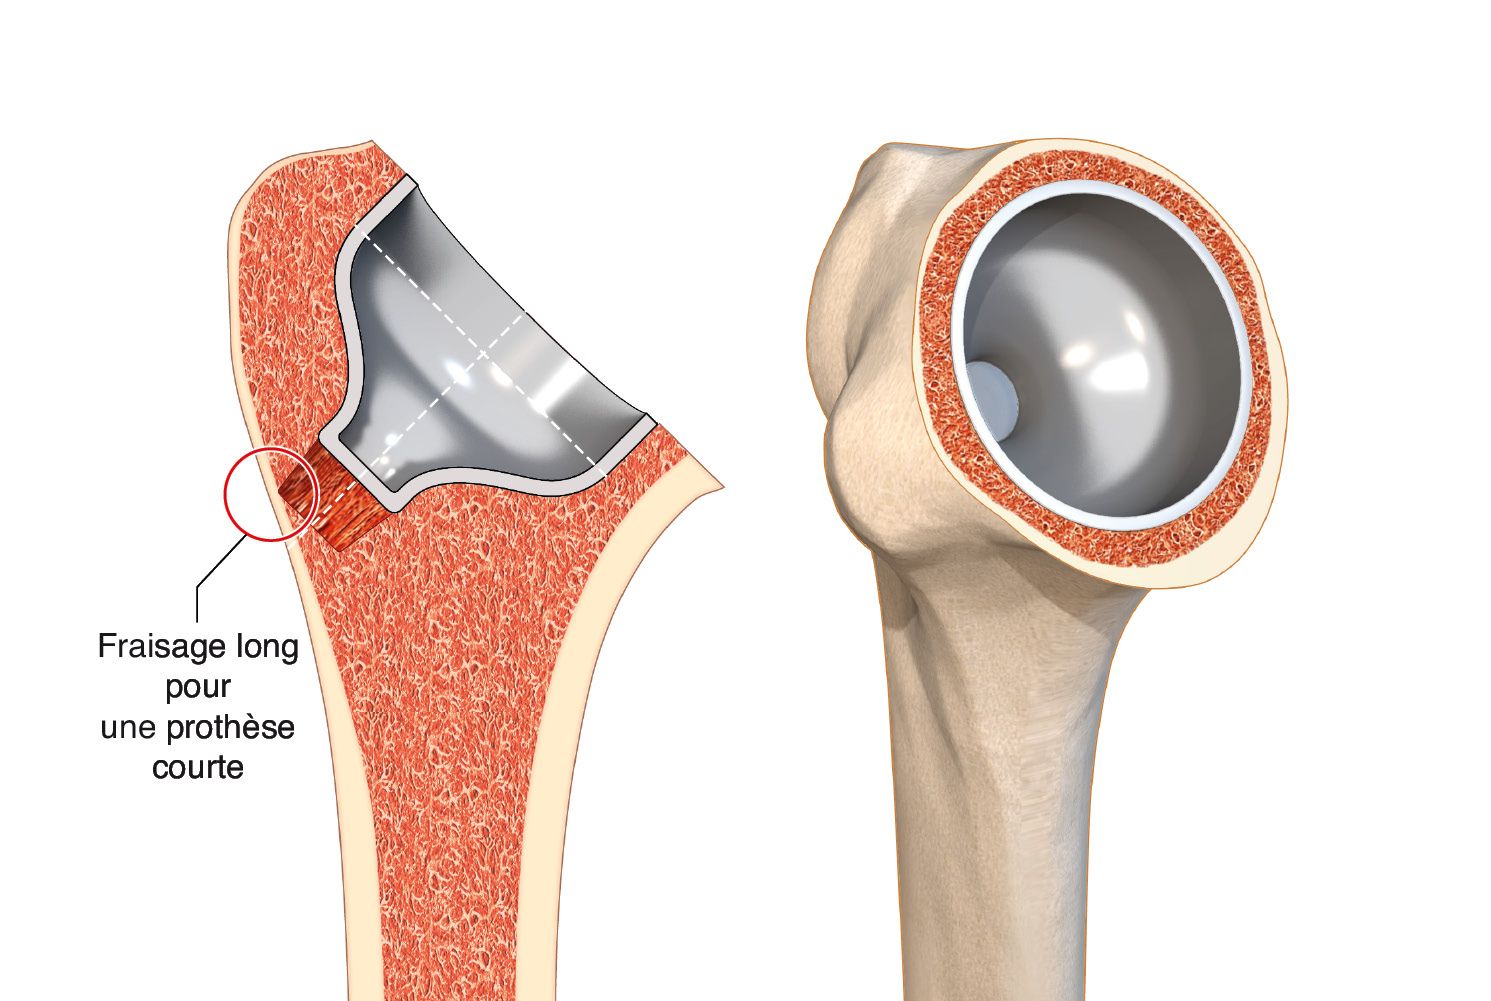

b. The implant is held in place by its ring, which must therefore fit perfectly into the metaphysis. Make sure that the distal post is not touching the bone. (For the LIMA SMR, one solution is to ream for a long post but use a short post) (Fig. 13).